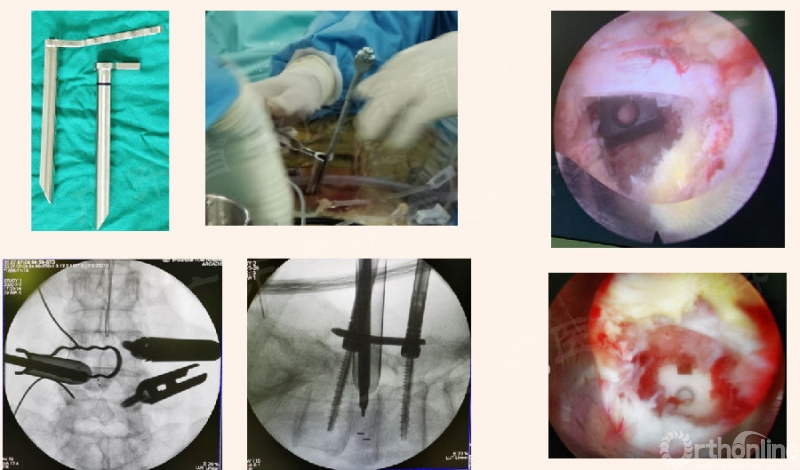

为进一步解决临床实际问题,本期内容将针对腰椎Endo-PTLIF的标准化流程,按照手术常规步骤中椎管外、进入椎管、椎管内的操作进行介绍,详见下文。

进入椎管的相关操作

椎管内的相关操作

1. 椎间盘显露及开口

4. 工作管-鸭舌管

5. 椎间盘处理

10. Cage置入:活动页片